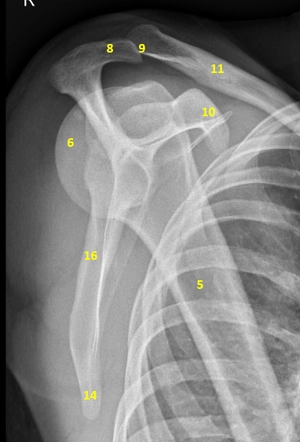

What is an X-ray Left Scapula AP & LAT View Test?

An X-ray of the scapula (shoulder blade) visualizes the shoulder blade and the surrounding soft tissues (skin and muscles). The scapula is a bone with a triangular shape that connects the collarbone to the upper arm bone and chest wall.